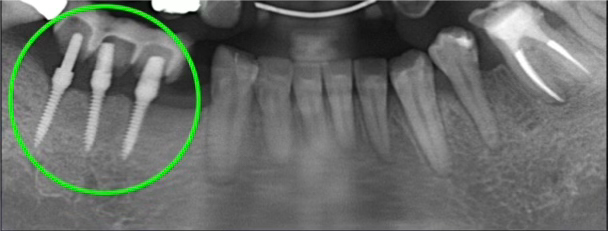

お口の中を拝見すると、昔、主流だった「歯周補綴(ししゅうほてつ)」という、すべての歯をつなげて固定する治療がされていました。

この方法は一見、硬くてしっかりしていますが、実は歯磨きが難しく、歯周病が進行しやすいという弱点があります。

さらに、どこか一部の歯にトラブルが起きても部分的に外すことができないため、最終的には“全ての歯を一度に失う”リスクを抱えています。

患者様の上の歯は全体的に大きく動揺しており、歯を支える骨がすでにかなり吸収していました。

このままでは全ての歯が抜け落ちてしまう可能性が高い状態でした。